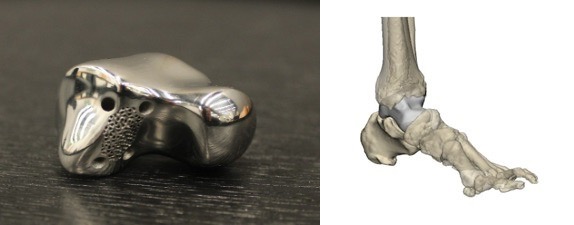

Addressing massive bone loss and avascular necrosis through high-fidelity anatomical reconstruction. By utilizing patient-specific CT data, we developed a 3D-printed titanium talus that restores joint height and preserves natural range of motion where traditional fusion would have failed.